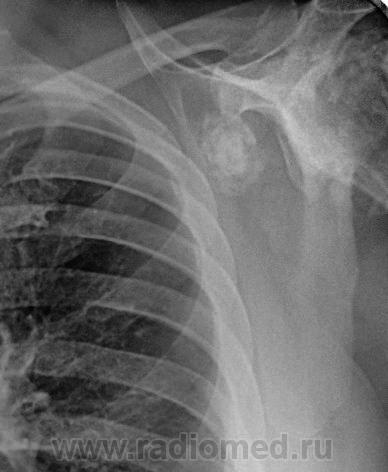

Пациент 60 лет, при прохождении проверочной флюорографии  обнаружены изменения со сторны плечевых суставов.Водитель троллейбуса.Страдает избыточной массой тела, люмбальгией, артороз коленных суставов.Непосредственно жалобы на плечевые суставы в медицинских документах не отражены. Какое будет мнение у коллег?

Пациент жалоб со сторны плечевых суставов не предъяляет и не помнит что бы когда- то что то беспокоило.Данных за сирингомиелию нет.

Александр, конечно надо доснять плечевые суставы... Из того, что есть: видимые отделы плечевых костей выглядят довольно симметрично, хотя слева и похуже, думаю - артроз. Весьма настораживает левая лопатка на предмет хондросаркомы

Снимки плечевых суставов.

Уважаемый Александр, приходиться признать, что на цифровой рентгенограмме легких изменения плечевых суставов видны лучше, чем на "обрезаных" и недоэкспонированых снимках суставов. По имеющимся данным могу только сказать, что деф. артроз с кистовидной перестройкой структуры есть. Под хрящевой опухолью (возможно - хондросаркома) левой лопатки я имела в виду тень, отмеченую красными стрелками, которая в поле снимка не вошла. Моя вина - в силу специфики работы такие узкоформатные снимки давно были вредными, т.к. очень часто патология остается за пределами снимка. Остается рекомендовать рентгенография левой лопатки в прямой передне-задней и косой проекциях, а лучше - КТ...